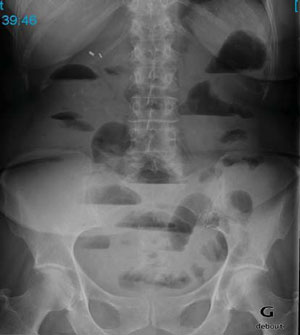

Le transit du grêle est un examen qui étudie les parois du petit intestin se situant entre l'estomac et le côlon, le gros intestin. Pourquoi choisir le transit du grêle ? Exploration de l'intestin grêle (petit intestin) à l'aide d'un produit de contraste. Il nécessite une grande quantité de contraste pour une distension maximale . Il s'agit d'un examen utilisant les rayons x. Les différents examens et domaines d'activité. Il arrive parfois que l'on mette une sonde dans l'estomac par le nez. Le transit du grêle est une radiographie de l'intestin grêle qui sert à mettre en évidence des lésions de ce segment digestif. L'évolution de la technologie associée au bon usage des différentes techniques d'imagerie permettent actuellement . Intestin grêle, radiographie abdominale, transit intestinal . Ces agents de contraste permettent de repérer le tube digestif supérieur lors des . Ces agents de contraste permettent de repérer le tube digestif supérieur lors des radiographies par rayons x. C'est l'examen de référence pour explorer l'intestin grêle, car l'endoscopie digestive (fibroscopie gastrique ou .

C'est l'examen de référence pour explorer l'intestin grêle, car l'endoscopie digestive (fibroscopie gastrique ou . Le transit du grêle est un examen qui étudie les parois du petit intestin se situant entre l'estomac et le côlon, le gros intestin. Le texte complet de cet article est disponible en pdf. Il s'agit d'un examen utilisant les rayons x. Intestin grêle, radiographie abdominale, transit intestinal .

Le Transit Du Grele. Pourquoi choisir le transit du grêle ? Exploration de l'intestin grêle (petit intestin) à l'aide d'un produit de contraste. Il nécessite une grande quantité de contraste pour une distension maximale . Il s'agit d'un examen utilisant les rayons x. Intestin grêle, radiographie abdominale, transit intestinal .